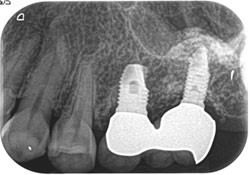

症例1

治療前

治療後

主訴 左上小臼歯から大臼歯部にかけて、脱離・歯冠崩壊、及び欠損があり、左奥では物が噛めない。

まだ年齢も50代と若く、義歯は煩わしく嫌であるという訴えがあり、左上5番・6番にインプラントを2本埋入する計画を立案。

副鼻腔までの距離がわずかしかないので、ソケットリフトと、骨の緻密化を計る為に、C・C・Wドリリング法を併用。

オぺから仮歯装着まで3ヶ月を要し、4ヶ月未満の治療期間を経て最終補綴物ジルコニア2本を装着。

リスクとしては、ソケットリフト(骨造成)による一過性の副鼻腔炎が起きる可能性がある。まれに洞底膜が破れる可能性がある。

ただし、膜は約3週で再生するので、膜の回復を待ち、再オペを行う。

費用 116万(オペ・ソケットリフト・人工骨・採血による濃縮血小板生成・仮歯・最終補綴物まで含む)